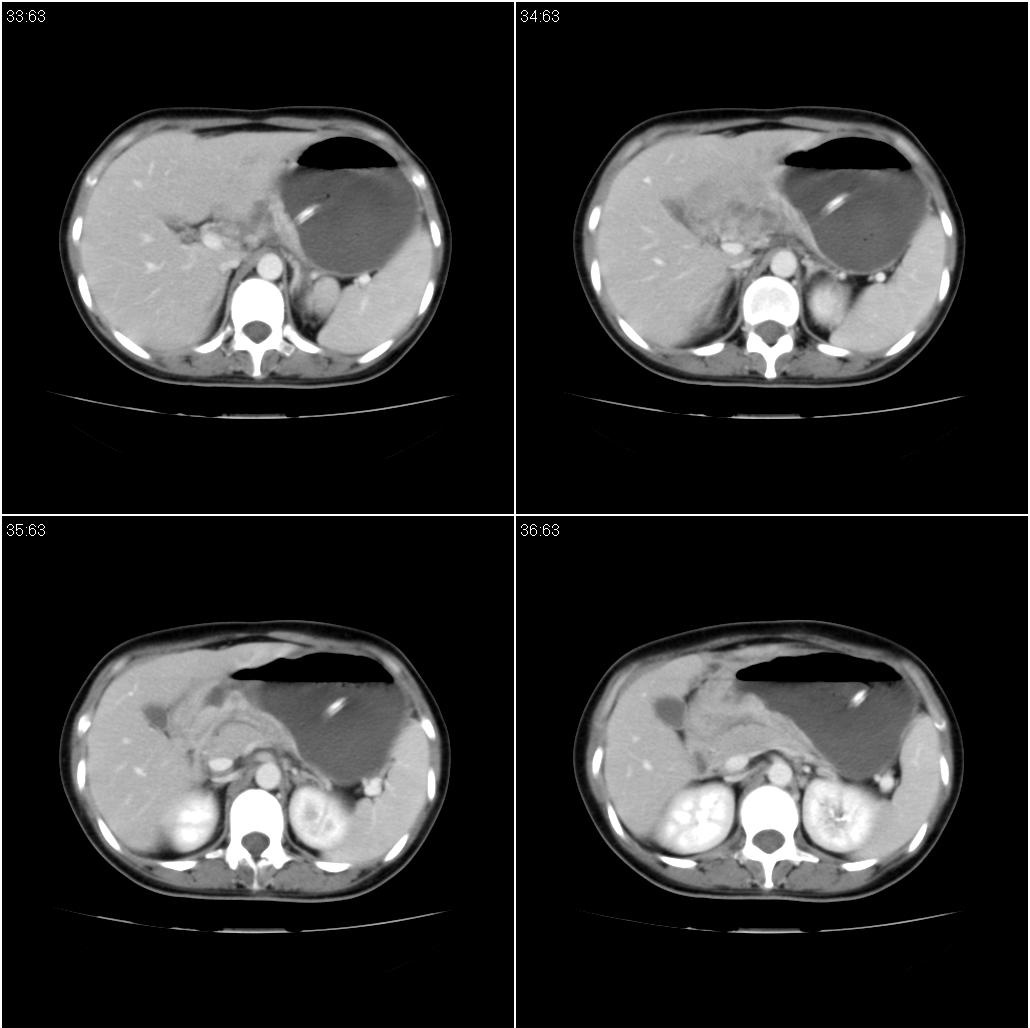

标题: CT21386:女性,33岁。4个月前因妊娠发现盆腔肿物。 [打印本页]

标题: CT21386:女性,33岁。4个月前因妊娠发现盆腔肿物。

女性,33岁。4个月前因妊娠发现盆腔肿物。ca-125: 1100

胃幽门部癌伴小弯侧和腹腔淋巴结转移,胃内有胃管。

有明显淋巴结吗?我们感觉像是胰腺和胃窦。不过,胰腺尤其是胰头较大,不知道是否正常?

胃窦贲门胃小弯好像都厚啊 ,胃窦处比较明显,而且胃腔扩张明显,考虑胃癌伴梗阻。

未见明显肿大淋巴结,另肝脾大